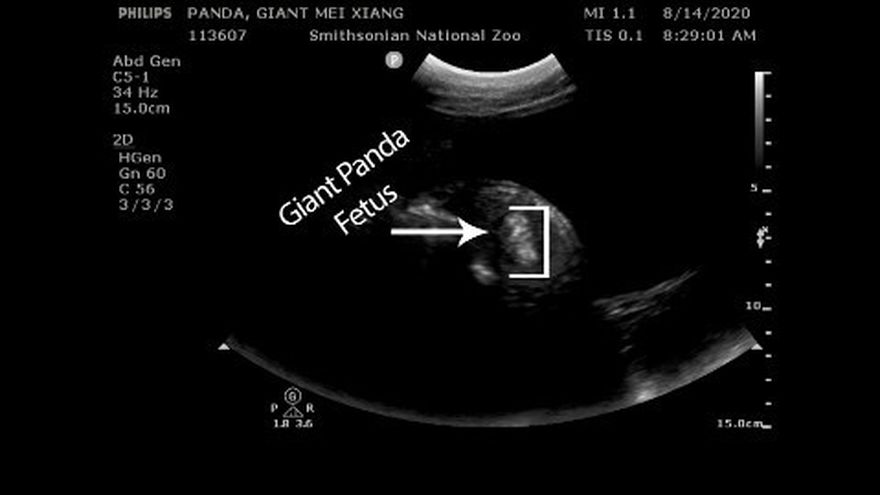

"¡Cruza las patas!", la hembra panda Mei Xiang tendrá un bebé en los próximos días, anunció el lunes el zoológico de Washington tras someterla una ecografía que reveló que el nuevo ejemplar en gestación crece sano.

Los veterinarios "vieron movimientos prometedores durante la ecografía de la panda gigante Mei Xiang", publicó el zoológico de la capital de Estados Unidos en Twitter. En el mensaje, agregó que "su feto pateaba y nadaba en líquido amniótico, y la columna y el flujo sanguíneo eran visibles".

"¡Esperamos tener un bebé sano en los próximos días!", agregó el Zoológico Nacional del Smithsonian, que publicó una imagen del estudio.